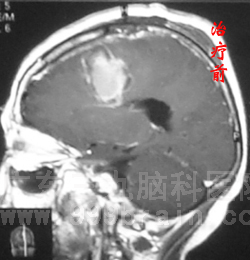

近日,55岁的苏女士回院复查,结果喜人:头颅MR检查未见复发迹象!这已是苏女士术后的第六个年头,复查结果意味着其病情已达到“临床治愈”标准!www.999brain.com

2006年8月,苏女士因突发肢体抽搐2天在当地医院查出左额颞叶占位性病变,大小约4.7×4.5×5.1cm,随即到广东三九脑科医院神经外科求诊。顺利接受手术治疗后,病理检查为少突星形细胞瘤Ⅱ-Ⅲ级,属恶性程度较高的胶质瘤,术后予以放化疗后复查头颅MR显示肿瘤消失。随后几年来她定期复查,未见肿瘤复发征象。2009年12月复查发现原术区出现斑点状异常强化影,为防止肿瘤复发,行2程化疗,治疗后强化影消失。目前距初次治疗已经6年,苏女士状态良好,与常人无异。